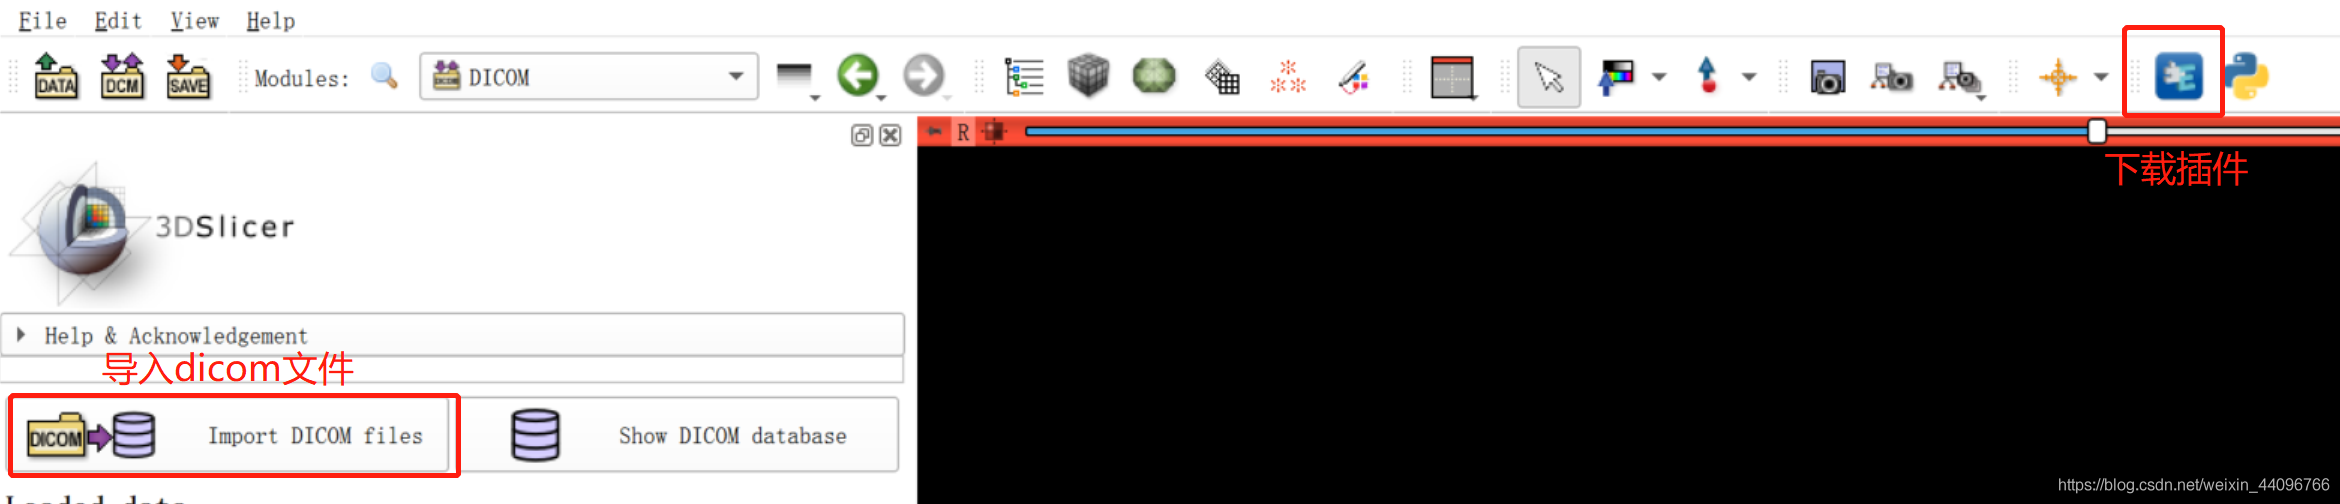

导入图片

- dicom格式图片通过import DICOM files导入

- nifit格式图片可以直接拖进去